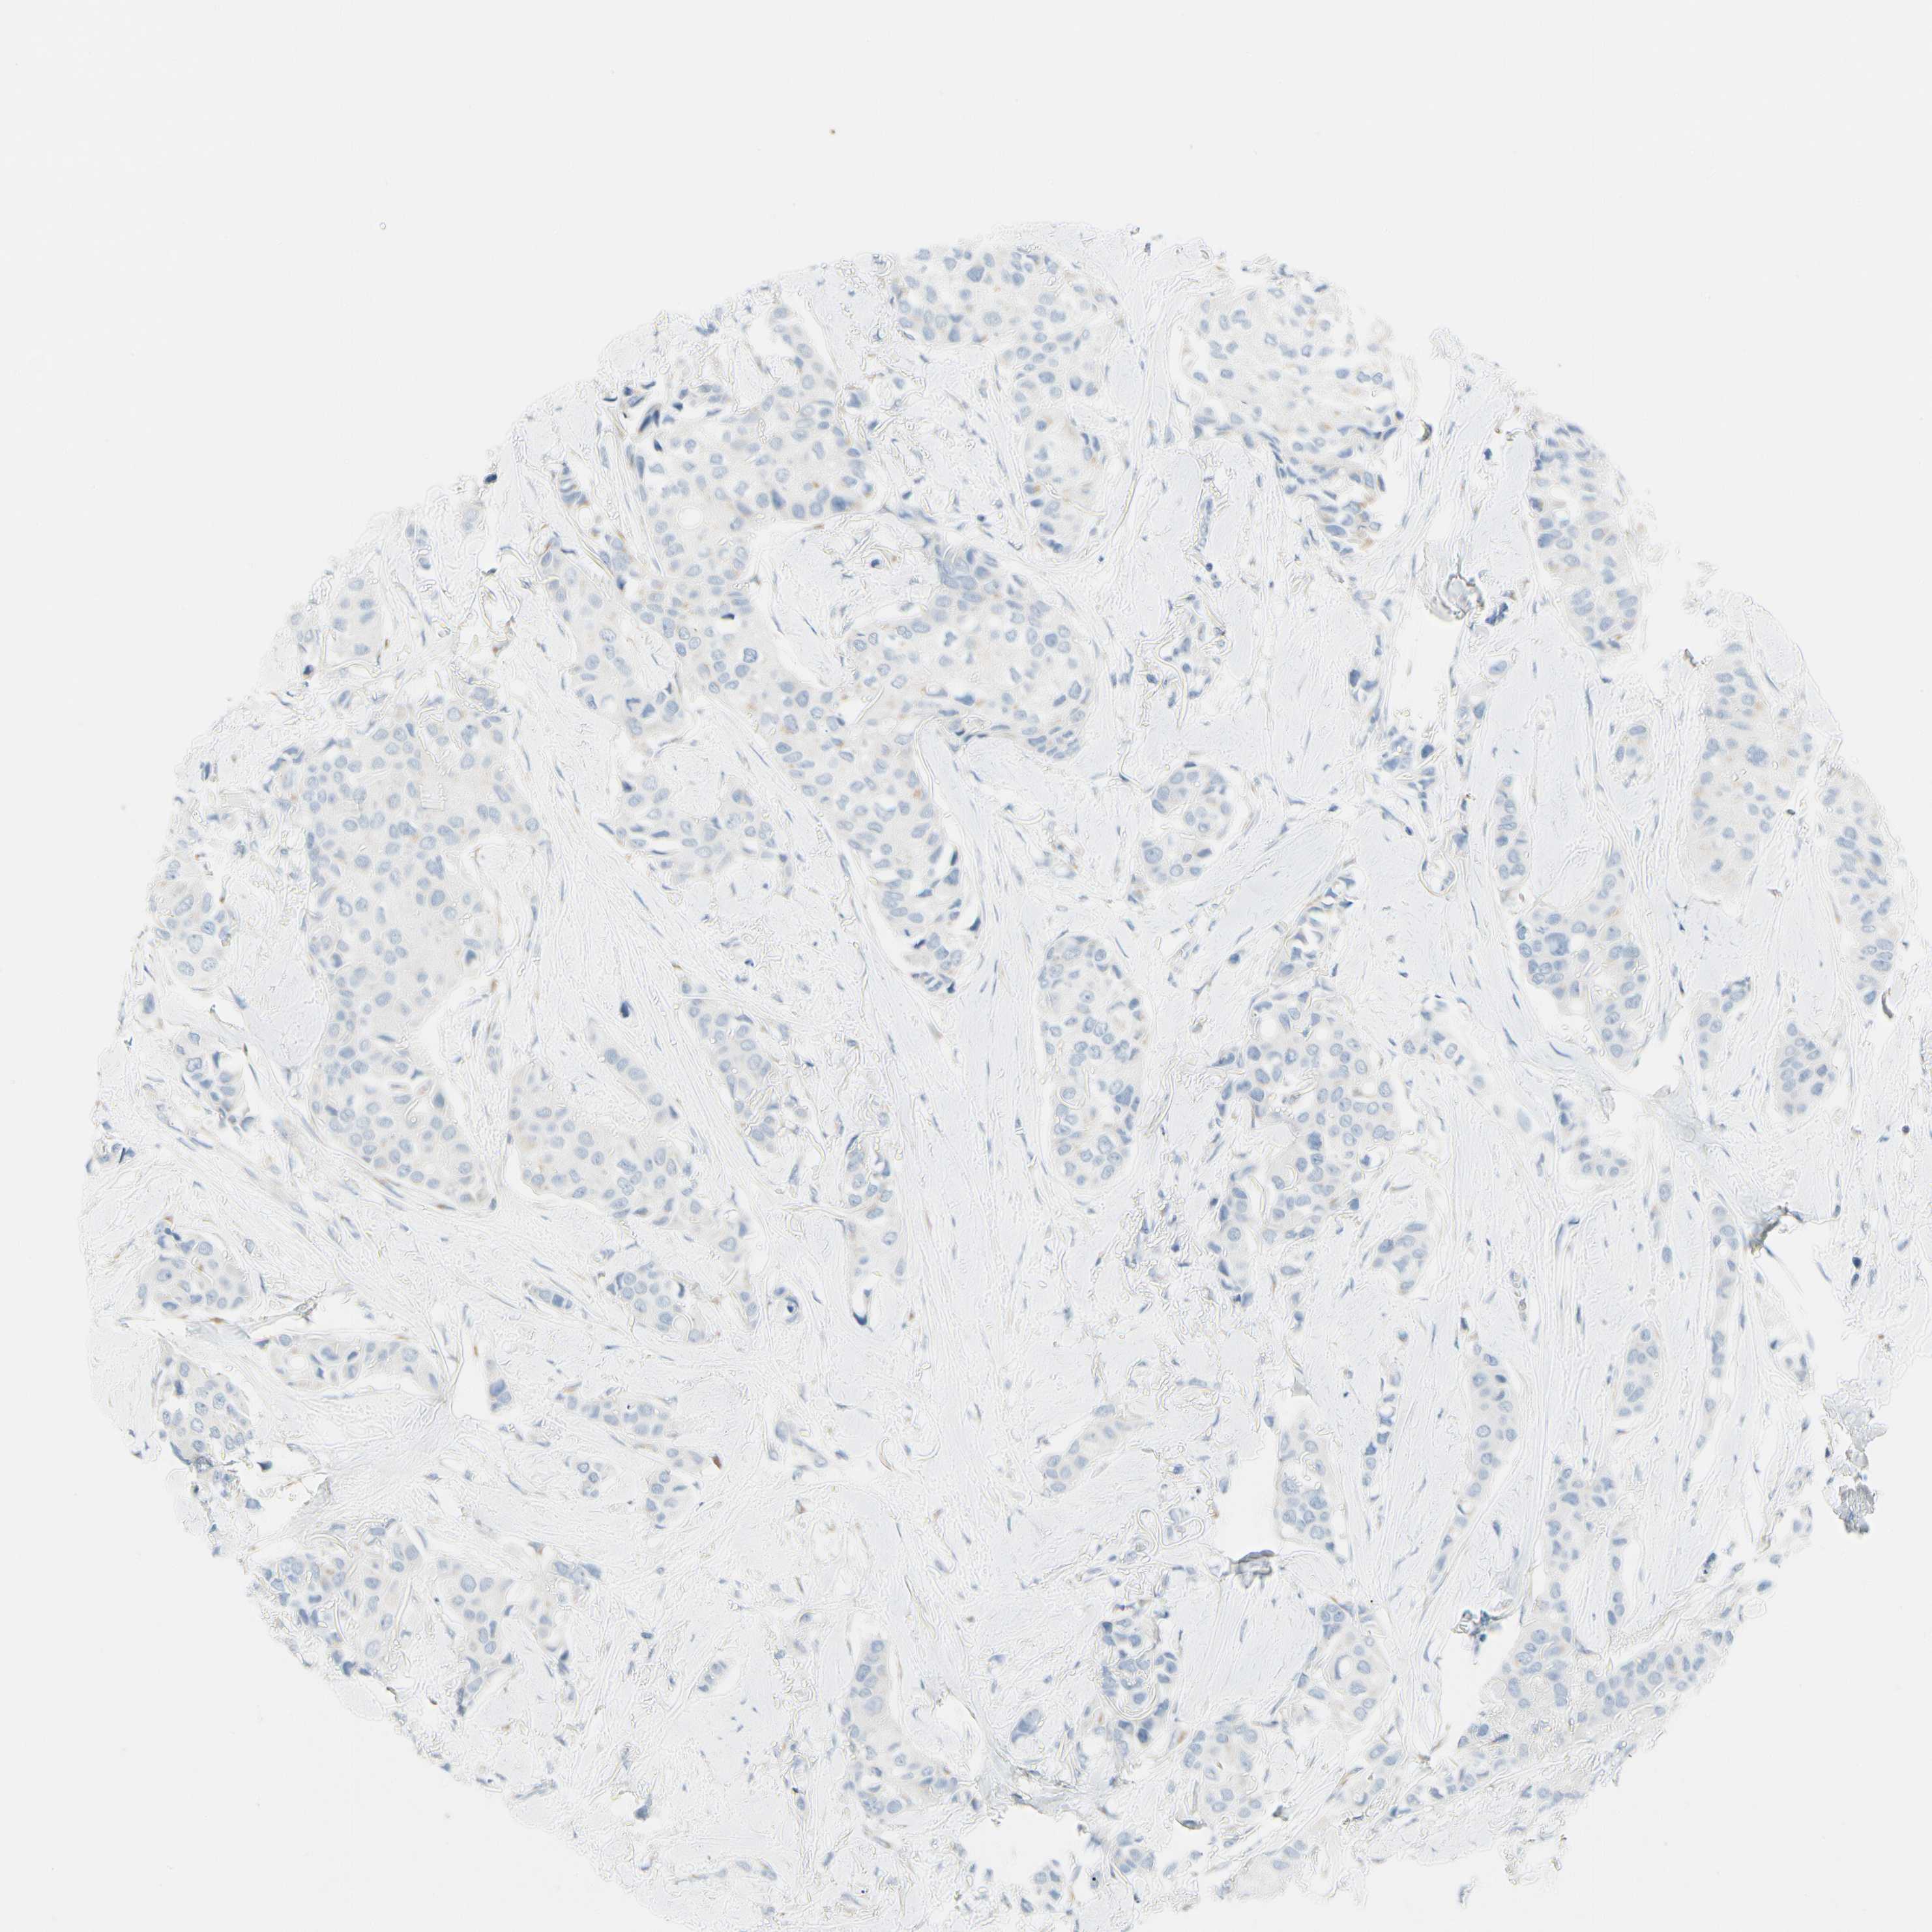

CANCER BREAST CANCER Show tissue menu

BRCA TCGA BRCA VALIDATION PROTEIN EXPRESSION